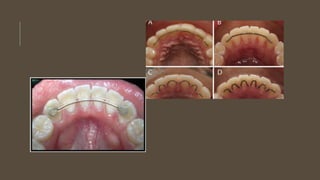

TIPOS DE RETENCIÓN Disponemosde dos tipos de retención, la que realizamos con aparatos removibles y la que realizamos con aparatos fijos. Retenedores removibles Son los realizados con acrílico y ganchos de retención metálicos O férulas transparentes

Uno de losmás populares es la placa de Hawley, tanto para el maxilar superior como para el inferior. Ventajas: son higiénicos y permiten corregir pequeñas irregularidades Inconvenientes: se necesita la colaboración del paciente

Férulas Transparentes Ventajas: Sonestéticas y se pueden confeccionar rápidamente. Inconvenientes: si se fracturan, no tienen reparación.

Retenedores fijos. Se utilizanbien cuando se proyecta una retención muy prolongada Cuando por problemas periodontales se teme por la estabilidad de la corrección o bien porque no confiemos en la colaboración del paciente. 1. Alambre rectangular 017×023 microarenado y perfectamente adaptado a las superficies linguales de los dientes que deseamos retener. Colocamos el alambre de modo que su mayor dimensión gingivo-oclusal se adapte a la superficie lingual de los dientes 2. Alambre trenzado entre los dientes extremos que deseamos retener 3. Barras que en sus extremos incorporan una base retentivapara cementarlas a los dientes

Ventajas: al serfijos, tenemos la seguridad de que los llevan. Inconvenientes: que se pueden descementar total o parcialmente. Cuando se descementan parcialmente, suele recidivar algún diente y nos plantea la necesidad de tener que corregir esta recidiva; cuando se descementa totalmente hay riesgo de que se lo pueda tragar el paciente. Dificultan la higiene, por lo que si el paciente no es muy cuidadoso, favorecen la acumulación de sarro.